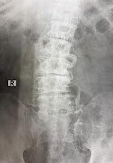

年が明けた頃より、院長が腰の痛みを訴えるようになってきました。以前より兆候があったので早く病院へ行くように勧めていたのに、ようやく重い腰を上げたようです。整形外科にてレントゲンを撮ってもらうと、やはり加齢による腰椎の変形からくるものらしく、痛み止めやリハビリで対処するしかないようです。(因みにレントゲンのコピーをもらったのでAIに相談してみたら、やはりしょうがないね…との答えでした。)